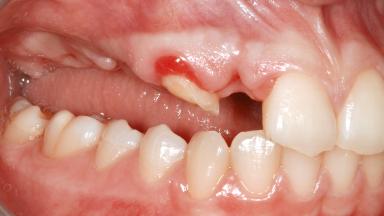

A 79-year-old female patient was referred to the Department of Periodontology of the University of Bern, Switzerland by her private dentist in May 2019. She had been rehabilitated in May 2005 with two tissue-level implants (Institut Straumann AG, Basel Switzerland) at sites 13 and 15, supporting a three-unit cemented fixed dental prosthesis (FDP). The metal-ceramic FDP had been cemented permanently with a glass-ionomer cement (Ketac Cem; 3M ESPE, Seefeld, Germany). Implant 13 had been diagnosed with peri-implant mucositis by the referring dentist in the course of regular supportive therapy. The patient was in good general health, did not smoke, and exhibited good self-performed plaque control.